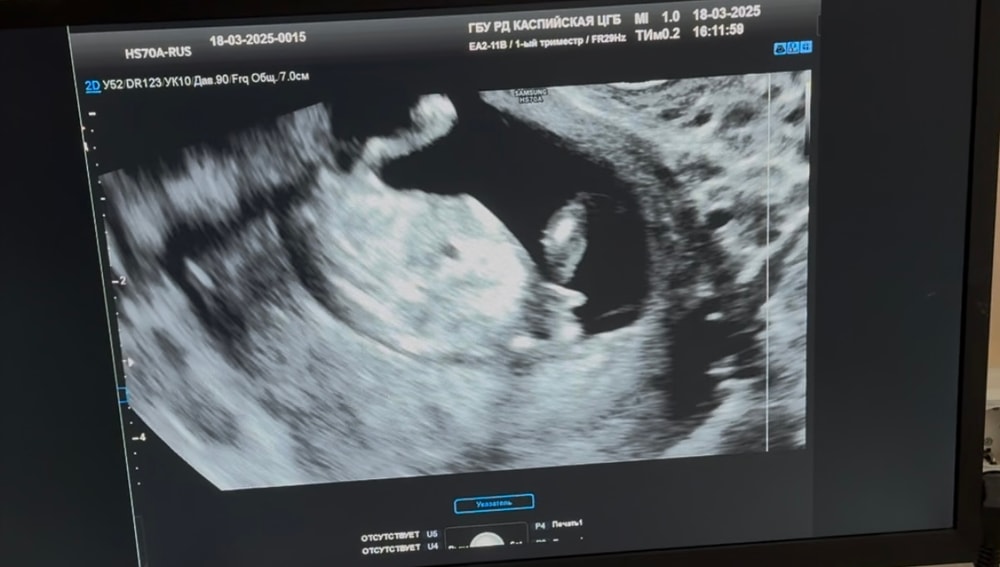

Если по крови девочка, то не сомневайтесь)) да, бывают ошибки, но это ооочень редко. По бугорку конечно малышка❤️

По узи видно, что девочка. Я тоже сдавала кровь и тоже девочка. На каждом узи прям переживала, что а вдруг мальчик) Не, и на 1, и на 2 скрининге, и потои на узи в 27 недель сказали, что девочка

Да,тут хорошо видно

Светлана , по расположению бугорка,тут хорошо видно градус, немного завалено на снимке,но если выровнять,то видно.

Планирование Пола ребёнка Определение пола по половому бугорку